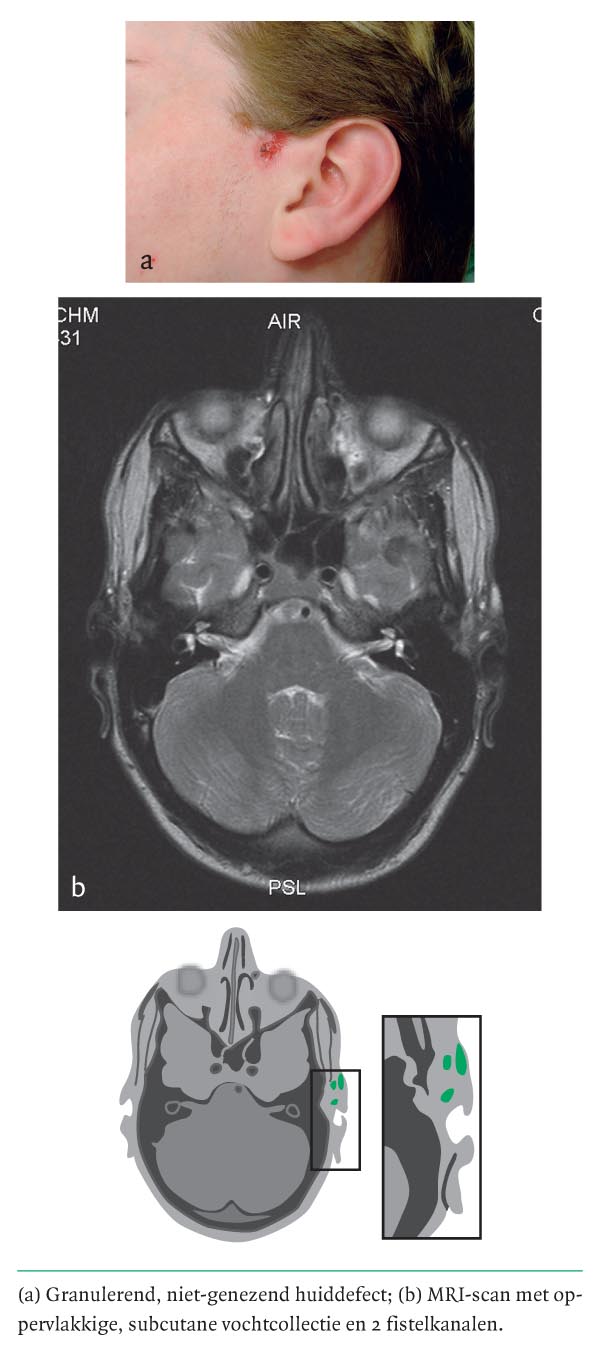

Een 23-jarige man presenteerde zich met craniaal van de tragus van beide oren gaatjes in de helix, die hij al sinds zijn geboorte had. Aan de linker kant waren deze enkele maanden eerder elders geëxploreerd omdat aan een geïnfecteerde epidermale cyste werd gedacht. Sindsdien manifesteerde zich preauriculair een niet-genezend wondje met persisterend vochtverlies. Bij onderzoek vonden wij een preauriculair granulerend huiddefect van 1 bij 1,5 cm (figuur a) met daarachter, craniaal van de tragus, een klein operatielitteken. Rechts was op dezelfde plaats in de helix ook een fistelopeningetje zichtbaar. Bij MRI werd links subcutaan een vochthoudende sinus…